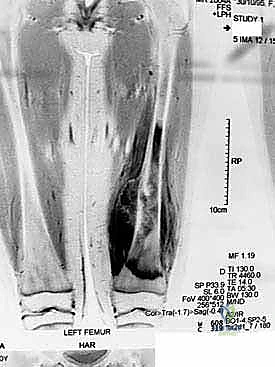

For any pediatric patient with a suspected or confirmed malignancy, an exhaustive staging imaging protocol is mandatory. Plain radiographs of the affected bone assess macroscopic bone destruction and periosteal reaction. Contrast-enhanced MRI of the entire affected bone is absolutely critical for defining intramedullary skip lesions and soft tissue tumor extension. The MRI dictates our planned level of bone transection, aiming for a minimum of 2-3 cm of normal marrow beyond the tumor extent. A high-resolution Chest CT is utilized to screen for pulmonary metastases, while an Isotope Bone Scan or PET-CT detects multifocal osseous disease.

Beyond standard oncologic staging, we require specialized orthopaedic measurements. Measured full-length scanograms of both the affected and contralateral limbs are critical for calculating current limb length and templating the prosthesis. A standardized hand/wrist radiograph is obtained to estimate skeletal bone age using the Greulich and Pyle atlas. This provides a vastly more accurate prediction of remaining growth than chronological age alone. The Estimated Limb-Length Discrepancy (LLD) at skeletal maturity is then calculated. While traditionally derived using the Anderson and Green charts, the validated Multiplier Method has emerged as a highly accurate and simpler predictor, utilizing chronological age and a single length measurement to definitively determine if an expandable prosthesis is indicated.

Neurovascular Topography of the Distal Femur and Proximal Tibia

The distal femur represents the most common site for pediatric osteosarcoma (approximately 52% of cases). The surgical approach is typically anteromedial, often involving a medial parapatellar arthrotomy. The primary neurovascular structures at risk include the femoral artery and vein, which lie posteromedial to the femur within the adductor canal and must be rigorously protected during posterior dissection, especially when defining posterior tumor margins. The popliteal vessels, located posterior to the knee joint and deep to the gastrocnemius, demand extreme care during posterior capsular release.